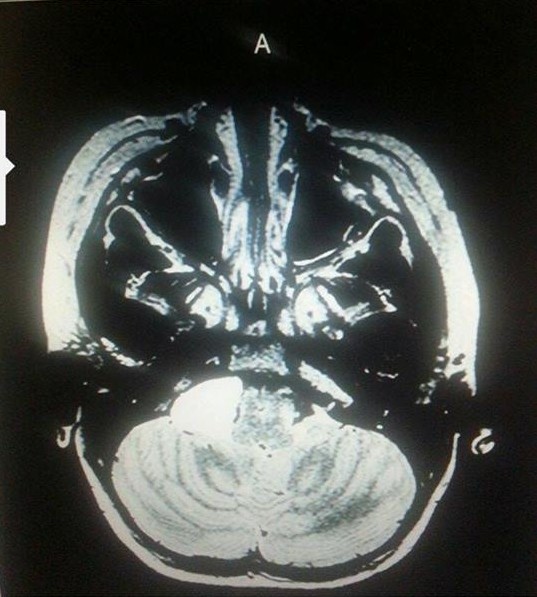

There were real diagnostic tests that matched the symptoms that backed up what was happening with both Kayla and Hannah Diegel, now age 11 and 13. One such example would be the MRI that showed a large arachnoid brain cyst pushing on Hannah’s brain stem.

Diegel brain scan

Hannah’s brain MRI. Source: Diegel family

This affected Hannah’s ability to walk (gait and balance), which caused numbness and tingling, vision problems, etc. Dr. Spetzler, the brain surgeon at St. Joseph’s Hospital, decided to do brain surgery to relieve the pressure. He did an excellent job. Hannah regained 100% of her balance, her vision improved enough where she didn’t even have to wear glasses anymore, and the numbness and tingling disappeared completely! It was miraculous! (She did, however, continue to have headaches.)